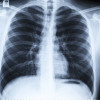

Halo dokter. Izin berdiskusi. Apabila ada pasien dengan hasil tapi test antigen reaktif samar, apakah tetap bisa kita diagnosis positif covid-19 atau sebaiknya pcr/antigen diulang (bila diulang pada hari yang sama atau beberapa hari setelahnya)?